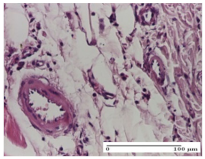

| AL Group | ![]() | ![]() | ![]() |

| vascular congestion and perivascular lymphocytes, Score 1 | inflammatory infiltrate in the hypodermis, Score 1 | periadnexal inflammatory infiltrate, Score 2 | |